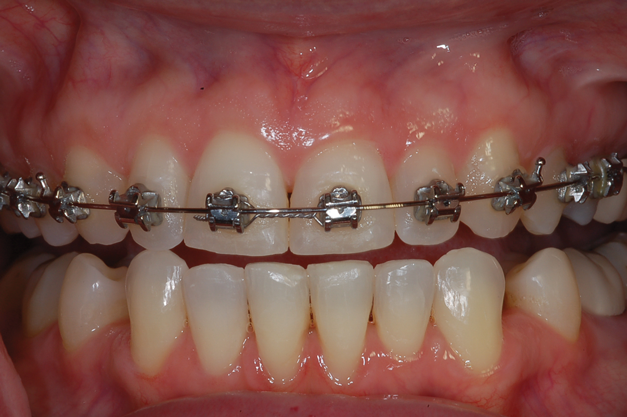

For orthodontic patients, the single clear tray used is 1.5-mm thick. Due to its thickness and the presence of the orthodontic brackets, the dentist takes a more active role in molding this clear tray intraorally. The tray is heated in the same manner as the previously discussed thermoplastic trays. Even when completely softened, it will not become imbedded into the brackets. When seating it, the path of insertion into the mouth should be slightly more facial to avoid engaging the tray edges on the brackets. The dentist must act quickly to seat the tray intraorally and begin applying pressure on the walls from the anterior to the posterior segments to adapt the tray over the brackets and onto the gingiva before it cools. As before, the patient will bite on his or her back teeth and produce suction to create a vacuum. When the tray has lost its heat, it is removed from the mouth, and the handle is removed with crown and bridge scissors. The patient or dentist may initially experience difficulty in determining the seat of the tray because the tooth molds are not as pronounced due to the presence of the orthodontic appliance. However, the tray will have a definite seat and fit once the path of insertion is found, and the patient should be able to insert and remove it easily (Figure 9).

(9.) A thermoplastic tray made directly in the mouth over orthodontic braces facilitates caries control and places the 10% carbamide peroxide into the braces to chemically and mechanically clean them.

Figure 9

(13.) Retracted view of a patient who had been using tray application of 10% carbamide peroxide for over a year to clean the braces as well as bleach the teeth.

Figure 13

(14.) Smile photograph of the patient in Figure 13 immediately after removal of the arch wires and brackets, showing no white spot lesions or any yellow spots where the the bonded brackets were previously located.

Figure 14